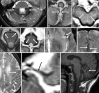

Despite extensive imaging, a source of bleeding is often not evident during the evaluation of patients with superficial siderosis (SS) of the central nervous system. An intraspinal fluid-filled collection of variable dimensions is frequently seen on spine MR imaging in patients with idiopathic SS. A similar finding has also been reported in patients with craniospinal hypotension. This review discusses the role of multitechnique imaging in the work-up of patients with SS and focuses on recent developments.